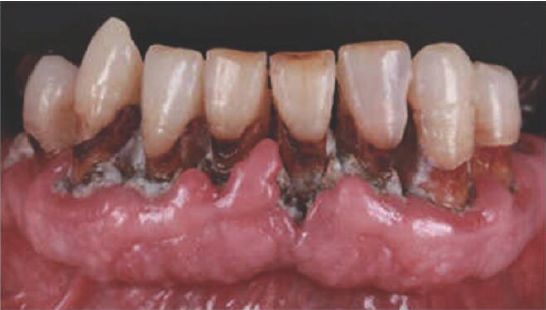

本届大会还举行了第一届临床摄影大赛。大赛分为3组:牙科疾病组、健康牙龈组和自由组。最后的获奖者是来自葡萄牙的 Honorato Vidal 医生。

健康牙龈组 Nikolaus Fürhauser(来自奥地利)作品